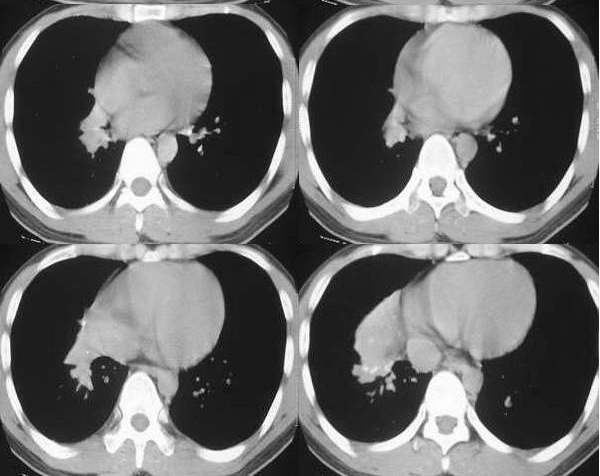

男,28岁,右胸不适,轻咳.余无特殊症状.请各位大侠发表见解

右肺下叶背段结核灶!肺门下方病灶没有传完整,不好说!看其形态,感觉象肺段实变,而且里面有散在点状钙化,不象是占位性病变.

右肺下叶背段结核灶,肺门软组织肿快影伴点壮钙化,考虑结核。纵隔淋巴结肿大。

右肺门区软组织肿块,边缘钙化,右肺中叶不张,右下叶背段结节状及斑片状影。首先考虑结核,建议支气管镜检查排除其他。

右肺门肿块,中叶支气管显示不清,纵隔肿大淋巴结。病人虽然年龄比较小。为什么不能考虑小细胞肺癌拌纵隔淋巴结转移?

右侧中间段支气管管壁增厚,管腔狭窄,形成块状软组织密度灶,右肺中叶膨胀不全,右肺下叶背段斑块状、片状阴影,且伴钙化,考虑:右侧中间段支气管内膜结核伴中叶不张、右肺下叶背段结核